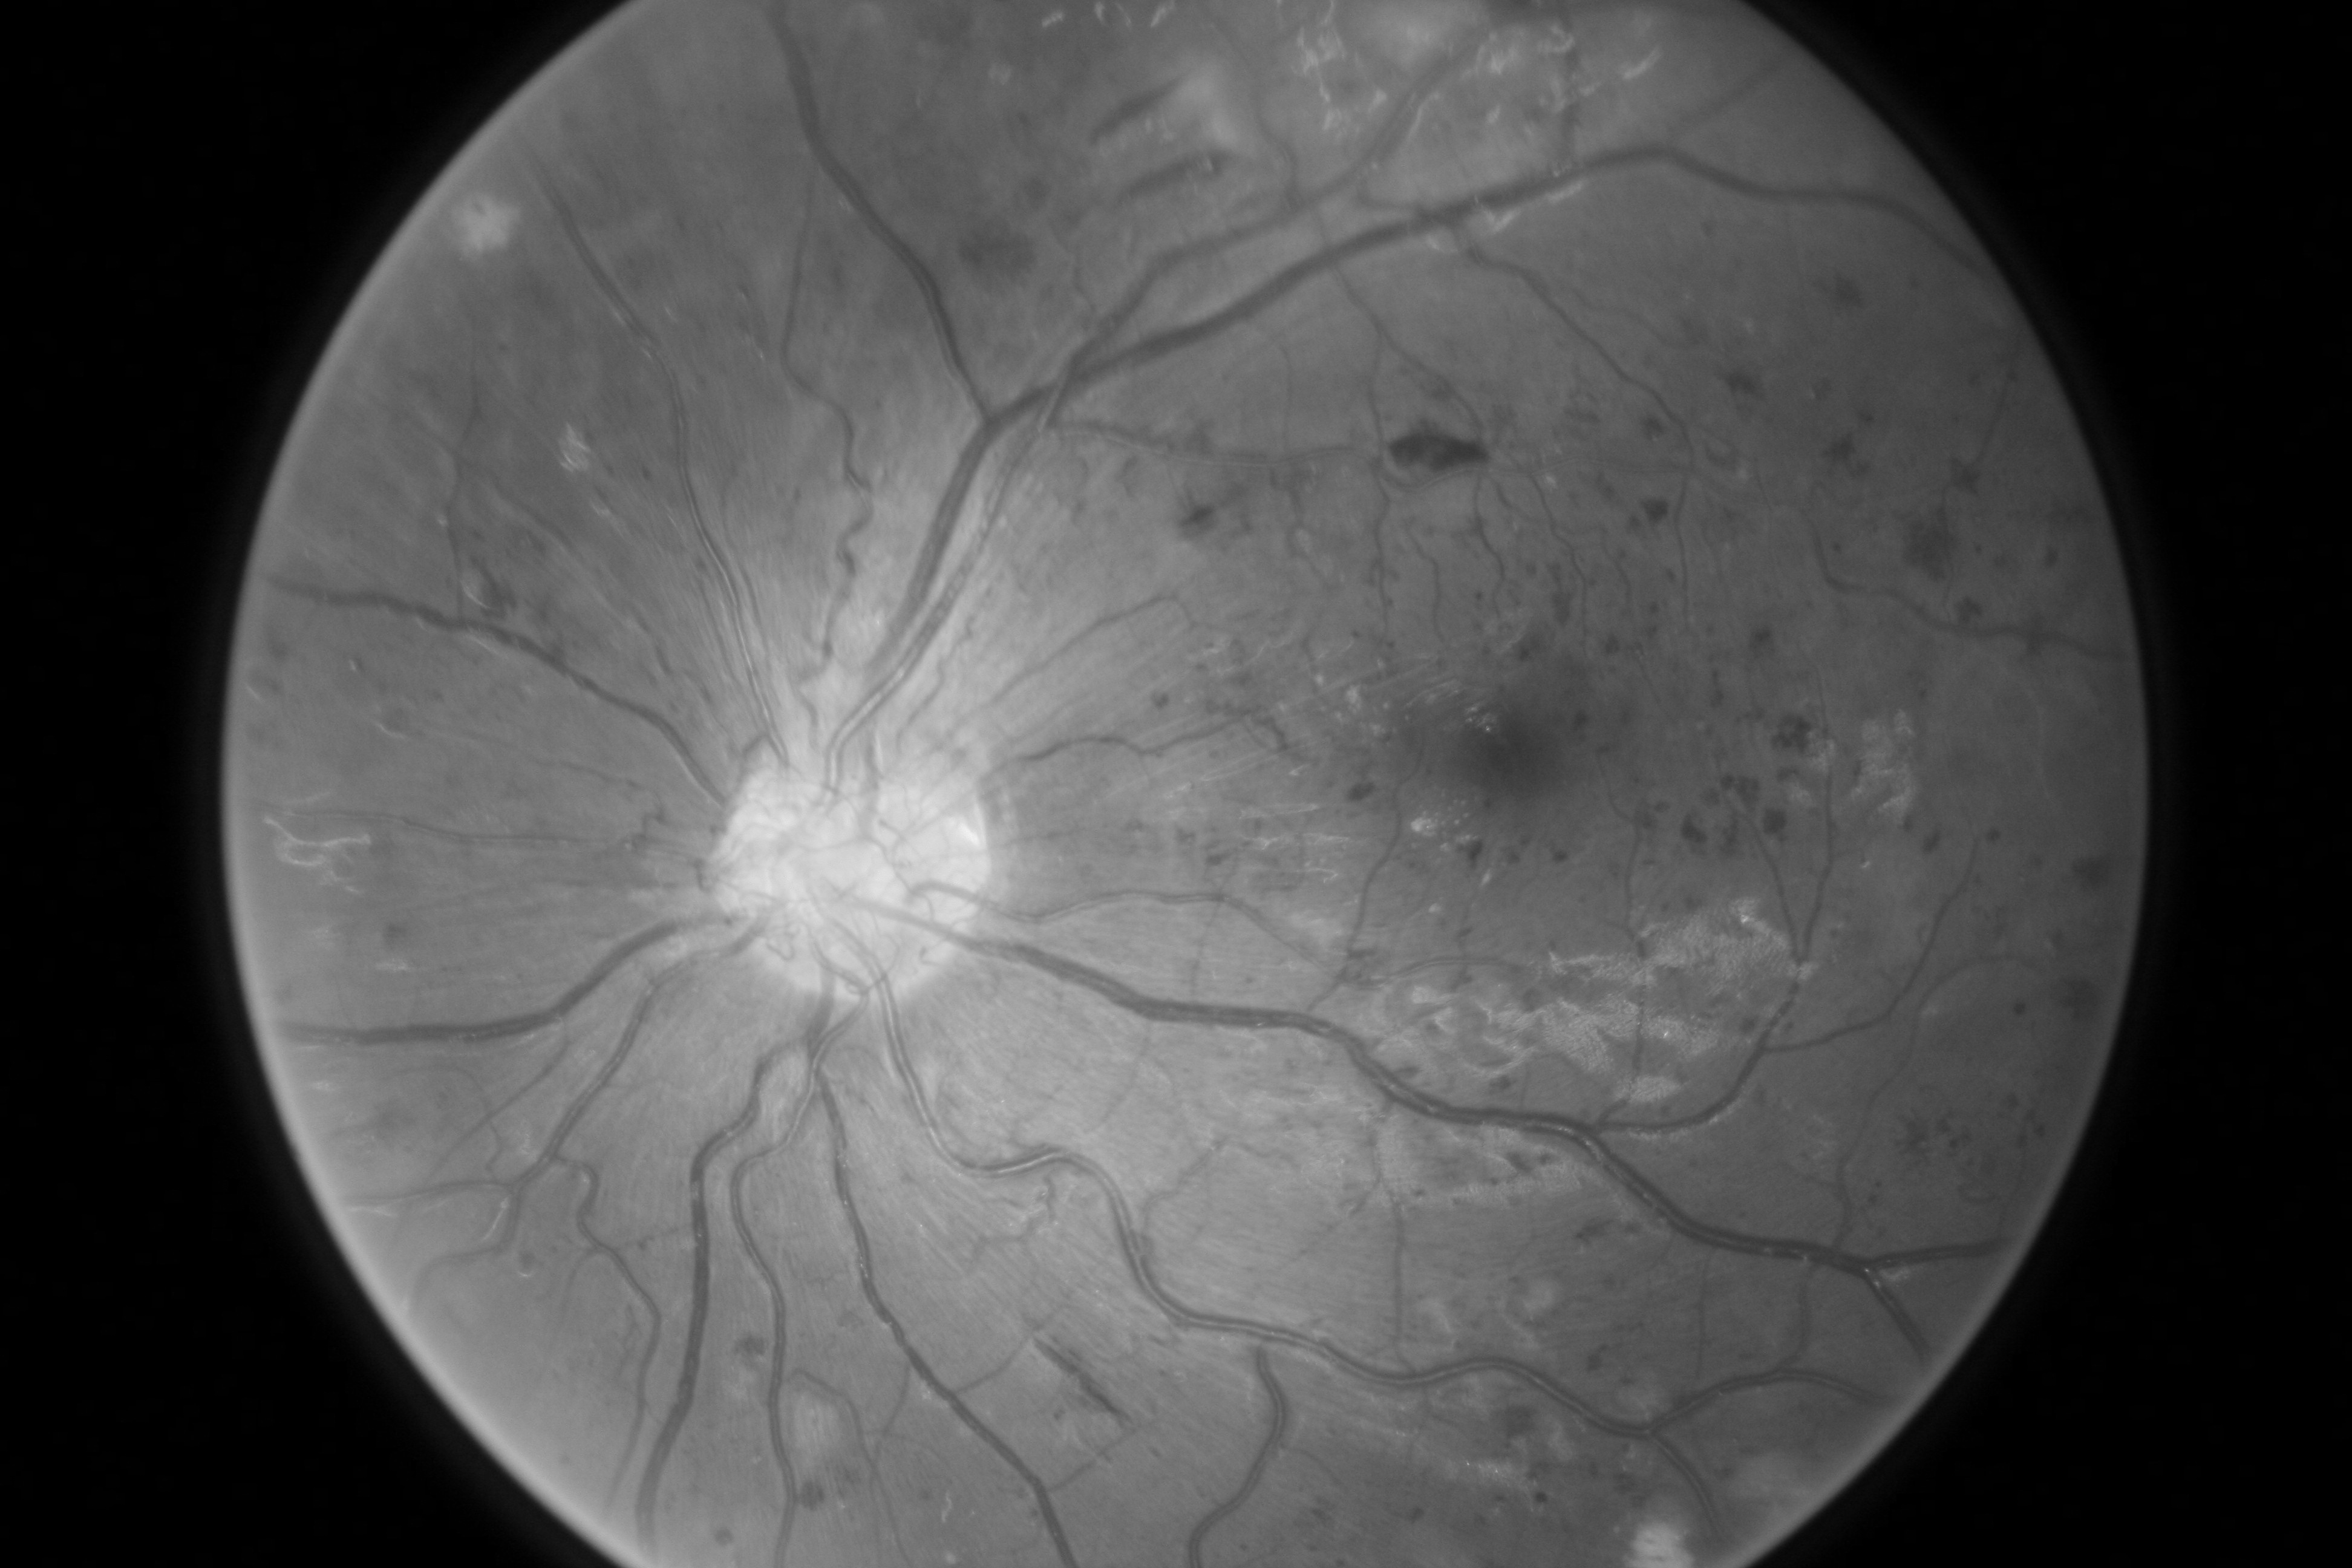

For completeness, and to test the robustness of our method, the models were also tested with several images sourced from Google™. We purposefully sourced extremely poor quality images (i.e. images with low contrast, speckle artefacts, etc), as well as images of pathological cases (i.e. Exdudates, Hemorrhages, etc). As there are no ground truth labels, only a qualitative assessment can be made of the results shown in Figure 2. In all cases, the models have accurately segmented the vessel structure whilst ignoring imaging artifacts and pathological lesions. This is very evident in the case of (5) and (6) where no vessels were segmented in areas of severe hemorrhaging.

{L to R: (1) Healthy, (2) Unhealthy, (3) Speckle Artefacts, (4) NPDR, (5) PDR, (6) Hemorrhages}